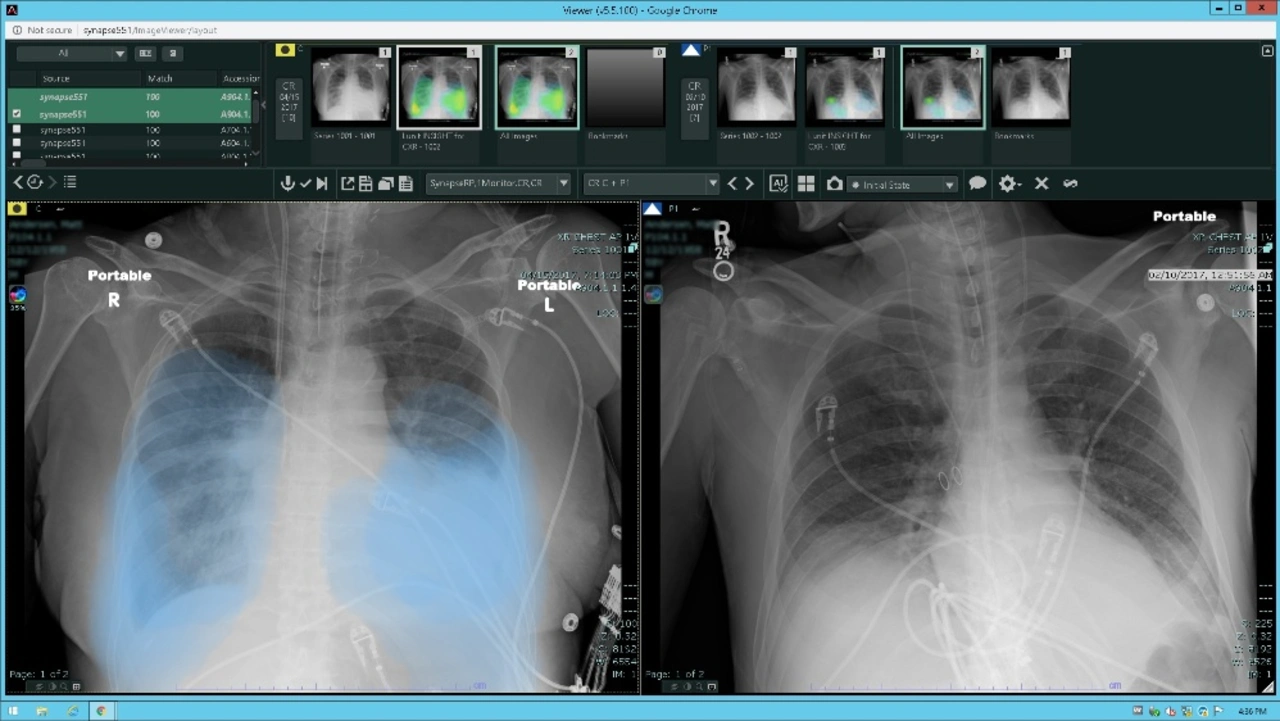

Künstliche Intelligenz (KI) ist ein hilfreiches Instrument zur Unterstützung des medizinischen Personals. In der COVID-19 Ausnahmesituation hat sich das ASST Krankenhaus in Vimercate (Italien) für REiLI entschieden und diese künstliche Intelligenz von Fujifilm Medical Systems implementiert.

»Die Unterstützung durch REiLI hat es unseren Radiologen ermöglicht, Untersuchungen schneller und effizienter zu reporten«, sagt Marcello Intotero, Leiter der Abteilung Radiology Structure and Diagnostics Services am ASST Vimercate. Zahlenmäßig hat sich ihre Arbeitsbelastung nicht besonders erhöht, da weniger dringliche Untersuchungen limitiert wurden, um einen übermäßigen Patientenfluss zu vermeiden. Diese neue Fujifilm-Technologie habe den Arbeitsablauf hervorragend unterstützt. Alle Aufnahmen, die von der KI als COVID-19-verdächtig identifiziert wurden, wurden von Radiologen schneller und mit höherer Priorität bearbeitet als andere Aufnahmen.

Die Verarbeitung von CT-Scans und Thorax-Röntgenaufnahmen durch REiLI stellt eine wichtige Unterstützung für den Radiologen dar und bietet ihm laut eigener Aussage eine extrem schnelle, quantitative und objektive Beurteilung der verschiedenen Zonen der Lunge. Insbesondere das Thoraxröntgen ist ein gutes Beispiel für die Anwendung der neuen KI-Technologie, da es sich um eine schnelle und einfache Untersuchung handelt, die eine Vielzahl nützlicher Informationen zur Bewertung der, durch das Virus verursachten, Lungenparenchym Konsolidierung liefert.

REiLI identifiziert verschiedene Befunde interstitieller Lungenentzündung, die auf CT-Bildern erscheinen, und berechnet deren Verteilung und Volumen.

Das Modul Lunit Insight CXR zur Analyse und Detektion der wichtigsten Lungenerkrankungen (Knötchen, Atelektase, Fibrose, Verkalkungen, Kardiomegalie usw.) ist in die REiLI-Plattform integriert. Aus gegebenem Anlass wurde das Modul aktualisiert, um bei der Identifizierung der durch das Virus verursachten Lungenparenchym Konsolidierung zu unterstützen.

REiLI wurde in nur zwei Wochen im ASST Krankenhaus in Vimercate installiert, zudem ein paralleles PACS, um den täglichen Arbeitsablauf nicht zu unterbrechen. Am 30. März 2020 war REiLI bereits in Betrieb genommen und hat in den ersten fünf Tagen mehr als 600 Bilder verarbeitet. Während der Corona-Notsituation wurden mehr als 900 Fälle von COVID-19 identifiziert, mit durchschnittlich 80 Röntgen-Thorax Untersuchungen pro Tag.

»Während des Notstands wurden im ASST täglich mehr als 80 Röntgenaufnahmen von stationären Patienten und Notfall-Patienten analysiert«, erklärt Giovanni Delgrossi, Leiter der IT-Abteilung des ASST Vimercate. Wenn für die Untersuchungen keine Priorität festgelegt wird, könne es Stunden dauern, bis ein bestimmtes Röntgenbild identifiziert ist, das unter Umständen ein sofortiges Handeln der Ärzte erfordert hätte. »In einem Notfall wie dem gegenwärtigen müssen wir noch schneller reagieren und handeln.«